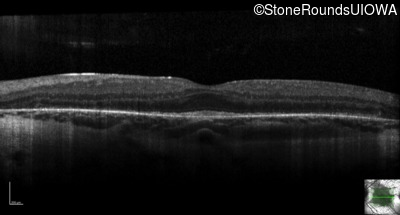

Optical Coherence Tomography - Left - 20/32 -2

Exemplar / OCT Stack

OCT Stack